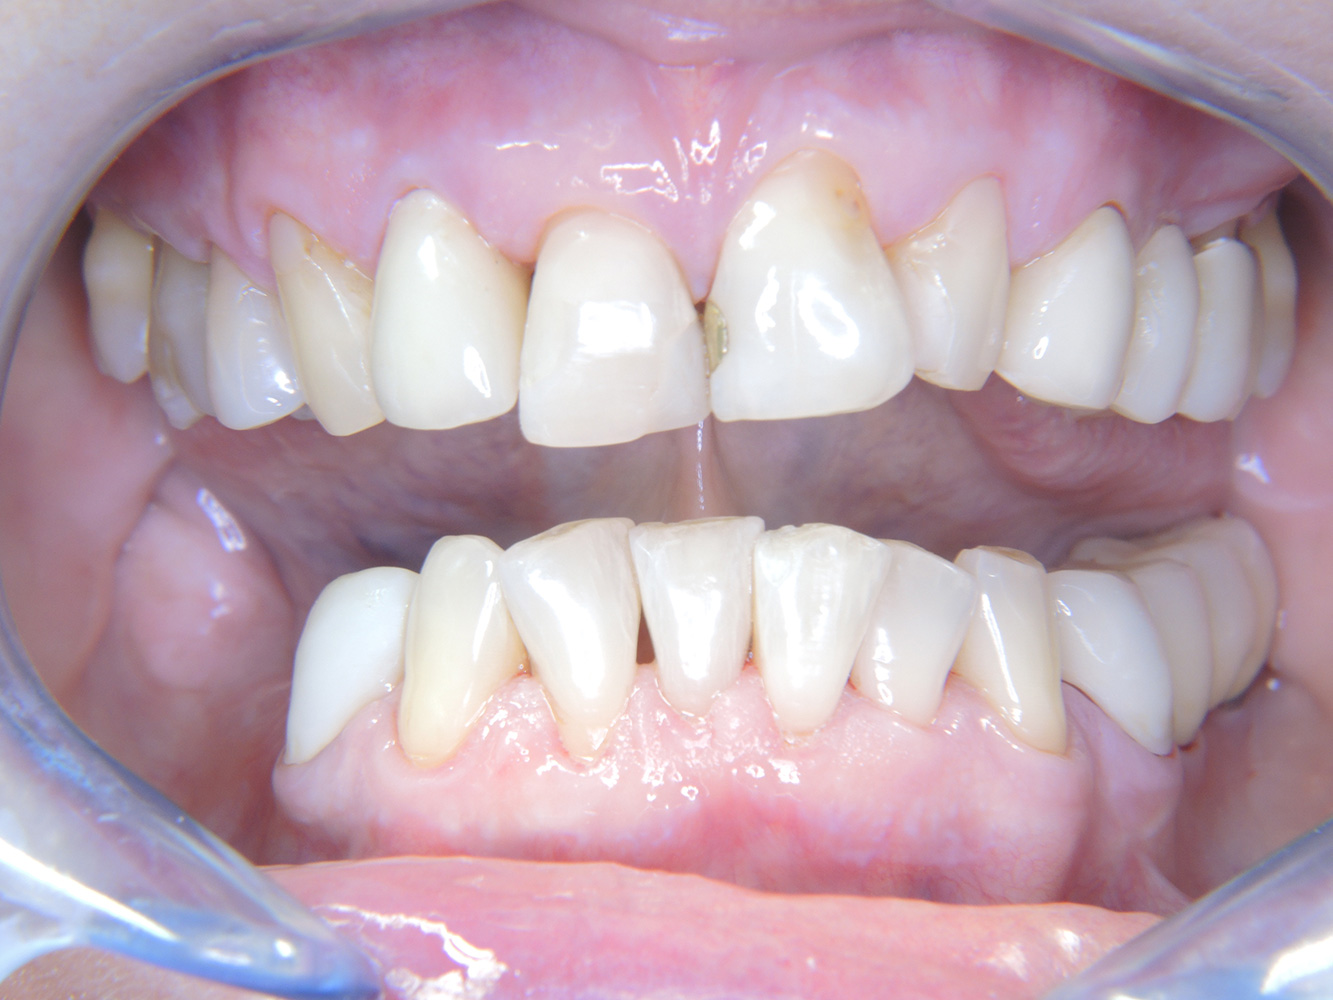

The 68-year-old patient has no general health conditions and is not taking any medication that may be relevant to her oral health, and her lifestyle does not pose any particular risk. The patient has two dental implants (3rd quadrant, for five years) and a previous case of periodontal disease (stage IV, grade B periodontitis) with tooth loss. Currently the periodontal conditions are stable. However, periodontitis significantly increases the biological complications of implantations and there is a risk of implant loss (21). Four recommendations can be determined for the prophylaxis session.

Despite the stable conditions, it is also crucial for the instructive/motivational discussion to be conducted with this patient. Particular attention should be paid to teaching the patient how to care for the implants correctly. Here in particular, good at-home maintenance can have a significant impact on the long-term stability of oral and implant health.

In terms of instruments, specific procedures are required for use with implants. In order to preserve the surface of the implant while cleaning it effectively, it is essential to choose suitable powders and instruments such as the targeted use of air polishing devices with special periodontal tips. Which powder is most suitable can be determined according to the needs and risk. For example, in addition to the appropriate degree of abrasion, dietary requirements (including sugar-free, low-salt) may also be taken into account.